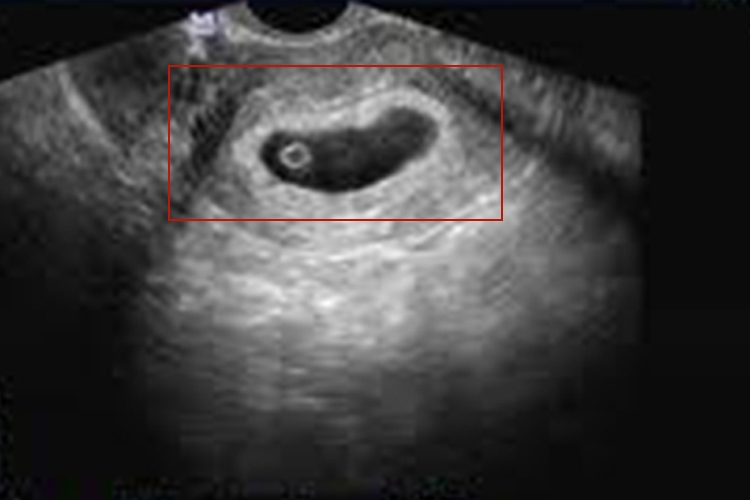

正常情况下怀孕初期妊娠囊外形多为圆形或椭圆形,特别细长考虑可通过超声检查发现,表现为中央极小的无回声区,小无回声区周边为一完整的、厚度均匀的强回声,整体呈细长形。若形状规则、边界清晰,位于子宫的中、上部,一般为正常现象,多注意观察即可。